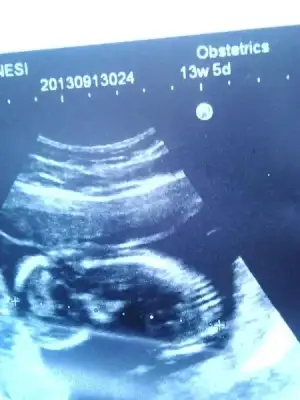

$IMG_0799.webp $IMG_0800.webp $IMG_0801.webp $IMG_0798.webp Merhaba arkadaşlar bende aranıza yeni katıldım.12 Haftalık hamileyim konuyu okuyunca dayanamadım yükledim resimleri.Bakarmısınız sizce ne olabilir bebişimin cinsiyeti

Kızlar fotograflar net deil doktorumuz bu konuda çok iyi değil güzel resim çekemiyor :1: ama gördgüğünüz kadarıyla tahmin söylersniz sevirinim :40::40: tşk :46: